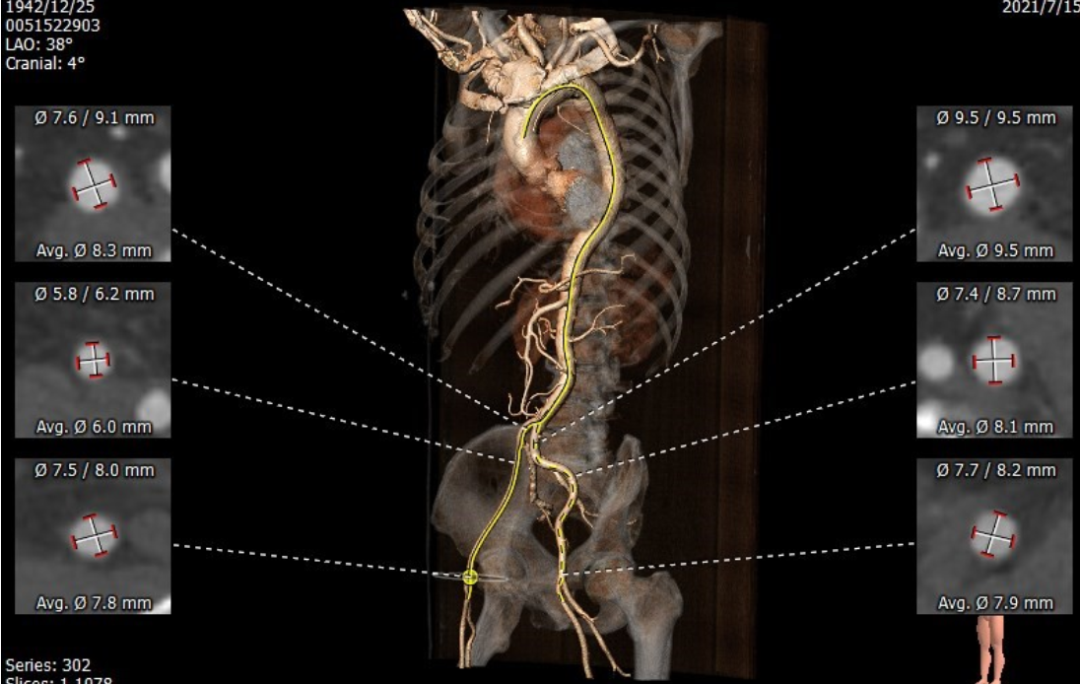

术前评估:

Annulus 22.6*27.5mm Perimeter=78.8mm

SOV 27.1*27.0*27.2mm

STJ 28.0*32.1mm

LVOT 21.5*28.7mm Perimeter=78.5mm

Ascending Aorta 38.7*40.1m

内径符合TAVI要求

该患者CT特点为:

功能性二叶瓣,左右融合,钙化集中于无冠窦,长条状钙化自瓣上延续至二尖瓣前叶,冠脉开口高度可,腹主动脉至髂动脉多发钙化,内径可,拟右股动脉入路,22mm球囊扩张,植入VitaFlow 27。